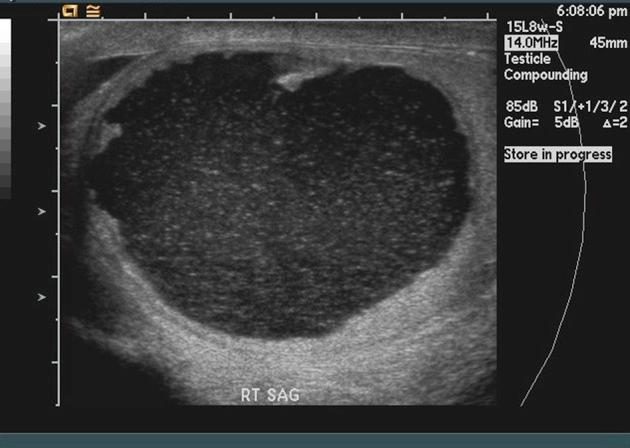

Serous borderline tumor (SBT) of the testis is a rare, ovarian epithelial-type tumor of the testis. We present a case of SBT after radical orchiectomy in a 59-year-old man who had 3-month progressive enlargement of his right hemi-scrotum, negative testicular tumor markers and scrotal ultrasound equivocal for malignancy. Magnetic resonance imaging (MRI) of the pelvis was obtained to aid with evaluation and showed marked hyperintensity on T2-weighted images with frond-like nodular peripheral enhancement within right testis mass. These distinct MRI findings can help clinicians differentiate SBT from other testis tumors. Relapse has not been observed in 8 years of follow-up.

睾丸浆液性交界性肿瘤(SBT)是一种罕见的睾丸卵巢上皮型肿瘤。我们报告一例59岁男性患者,在根治性睾丸切除术后发生SBT。该患者右侧半阴囊进行性肿大3个月,睾丸肿瘤标志物阴性,阴囊超声检查对恶性肿瘤的判断不明确。盆腔磁共振成像(MRI)用于辅助评估,结果显示右侧睾丸肿块在T2加权图像上呈明显高信号,周边有叶状结节样强化。这些独特的MRI表现有助于临床医生将SBT与其他睾丸肿瘤区分开来。随访8年未观察到复发情况。